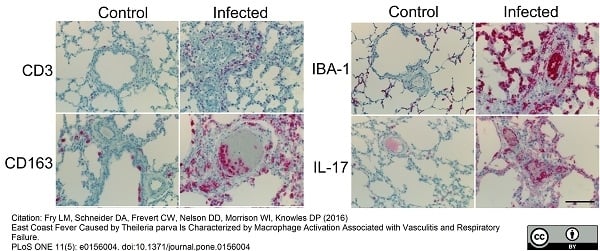

CD163, Monoclonal Antibody (Cat# AAA12256)